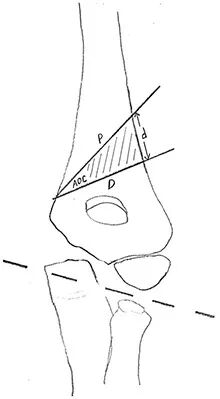

外侧突出指数lateral prominence index, LPI 反映了相对于肱骨轴线的内、外侧突出程度。其计算方法是:在肘关节前后位X线片上,分别测量最突出的内侧点和外侧点到肱骨轴线的距离,然后取两者的比值。截骨矫正中,如果未考虑 LPI,可能出现“外侧凸畸形(lateral bump)”:即矫正虽成功,但外侧骨皮质明显突出,影响美观甚至妨碍功能。术中实时测量或比对 LPI,可以提示是否需要进一步内侧平移或旋转调整,避免矫正过度或不足。

图片

外侧突出指数(%),公式为:(BC-AC)/AB×100。A,内侧突出;B,连接外侧突出的线之间的交叉连线;C,肱骨中部纵轴。